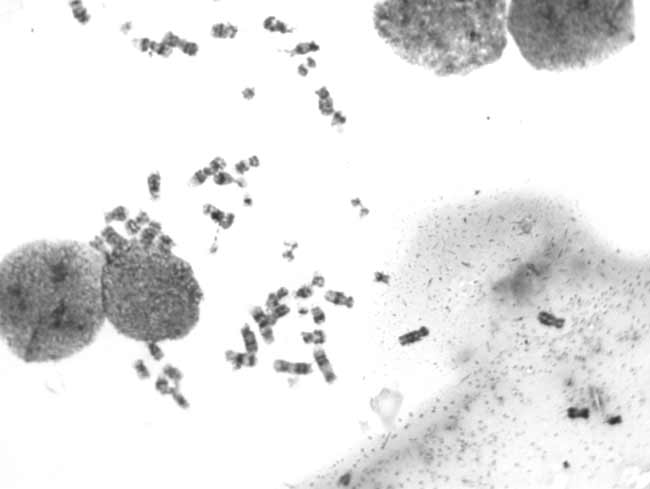

CCD and biogenetics——High sensitivity CCD Apply on chromosome shooting